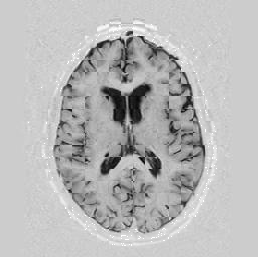

Another larger group of experiments enabled me to study the effects of multi-scale NRR. The results are shown in the form of chequerboard images in Figure [*]. In terms of resolution levels, higher numbers mean that the images are coarser.

Judging by some later stages when resolution is increased, the conclusion reached is that the added computational effort, which is enormous, makes this increase unneeded. The increase in resolution does not reveal much new information about the image structure, at least not at the stage when registration is still far from being entirely approached.

Figure: Multi-scale NRR (increasing resolution). From left to right, top then bottom:before NRR; after 5 iterations of NRR at level 2 (higher is coarser); after another 5 iterations of NRR at level 1.